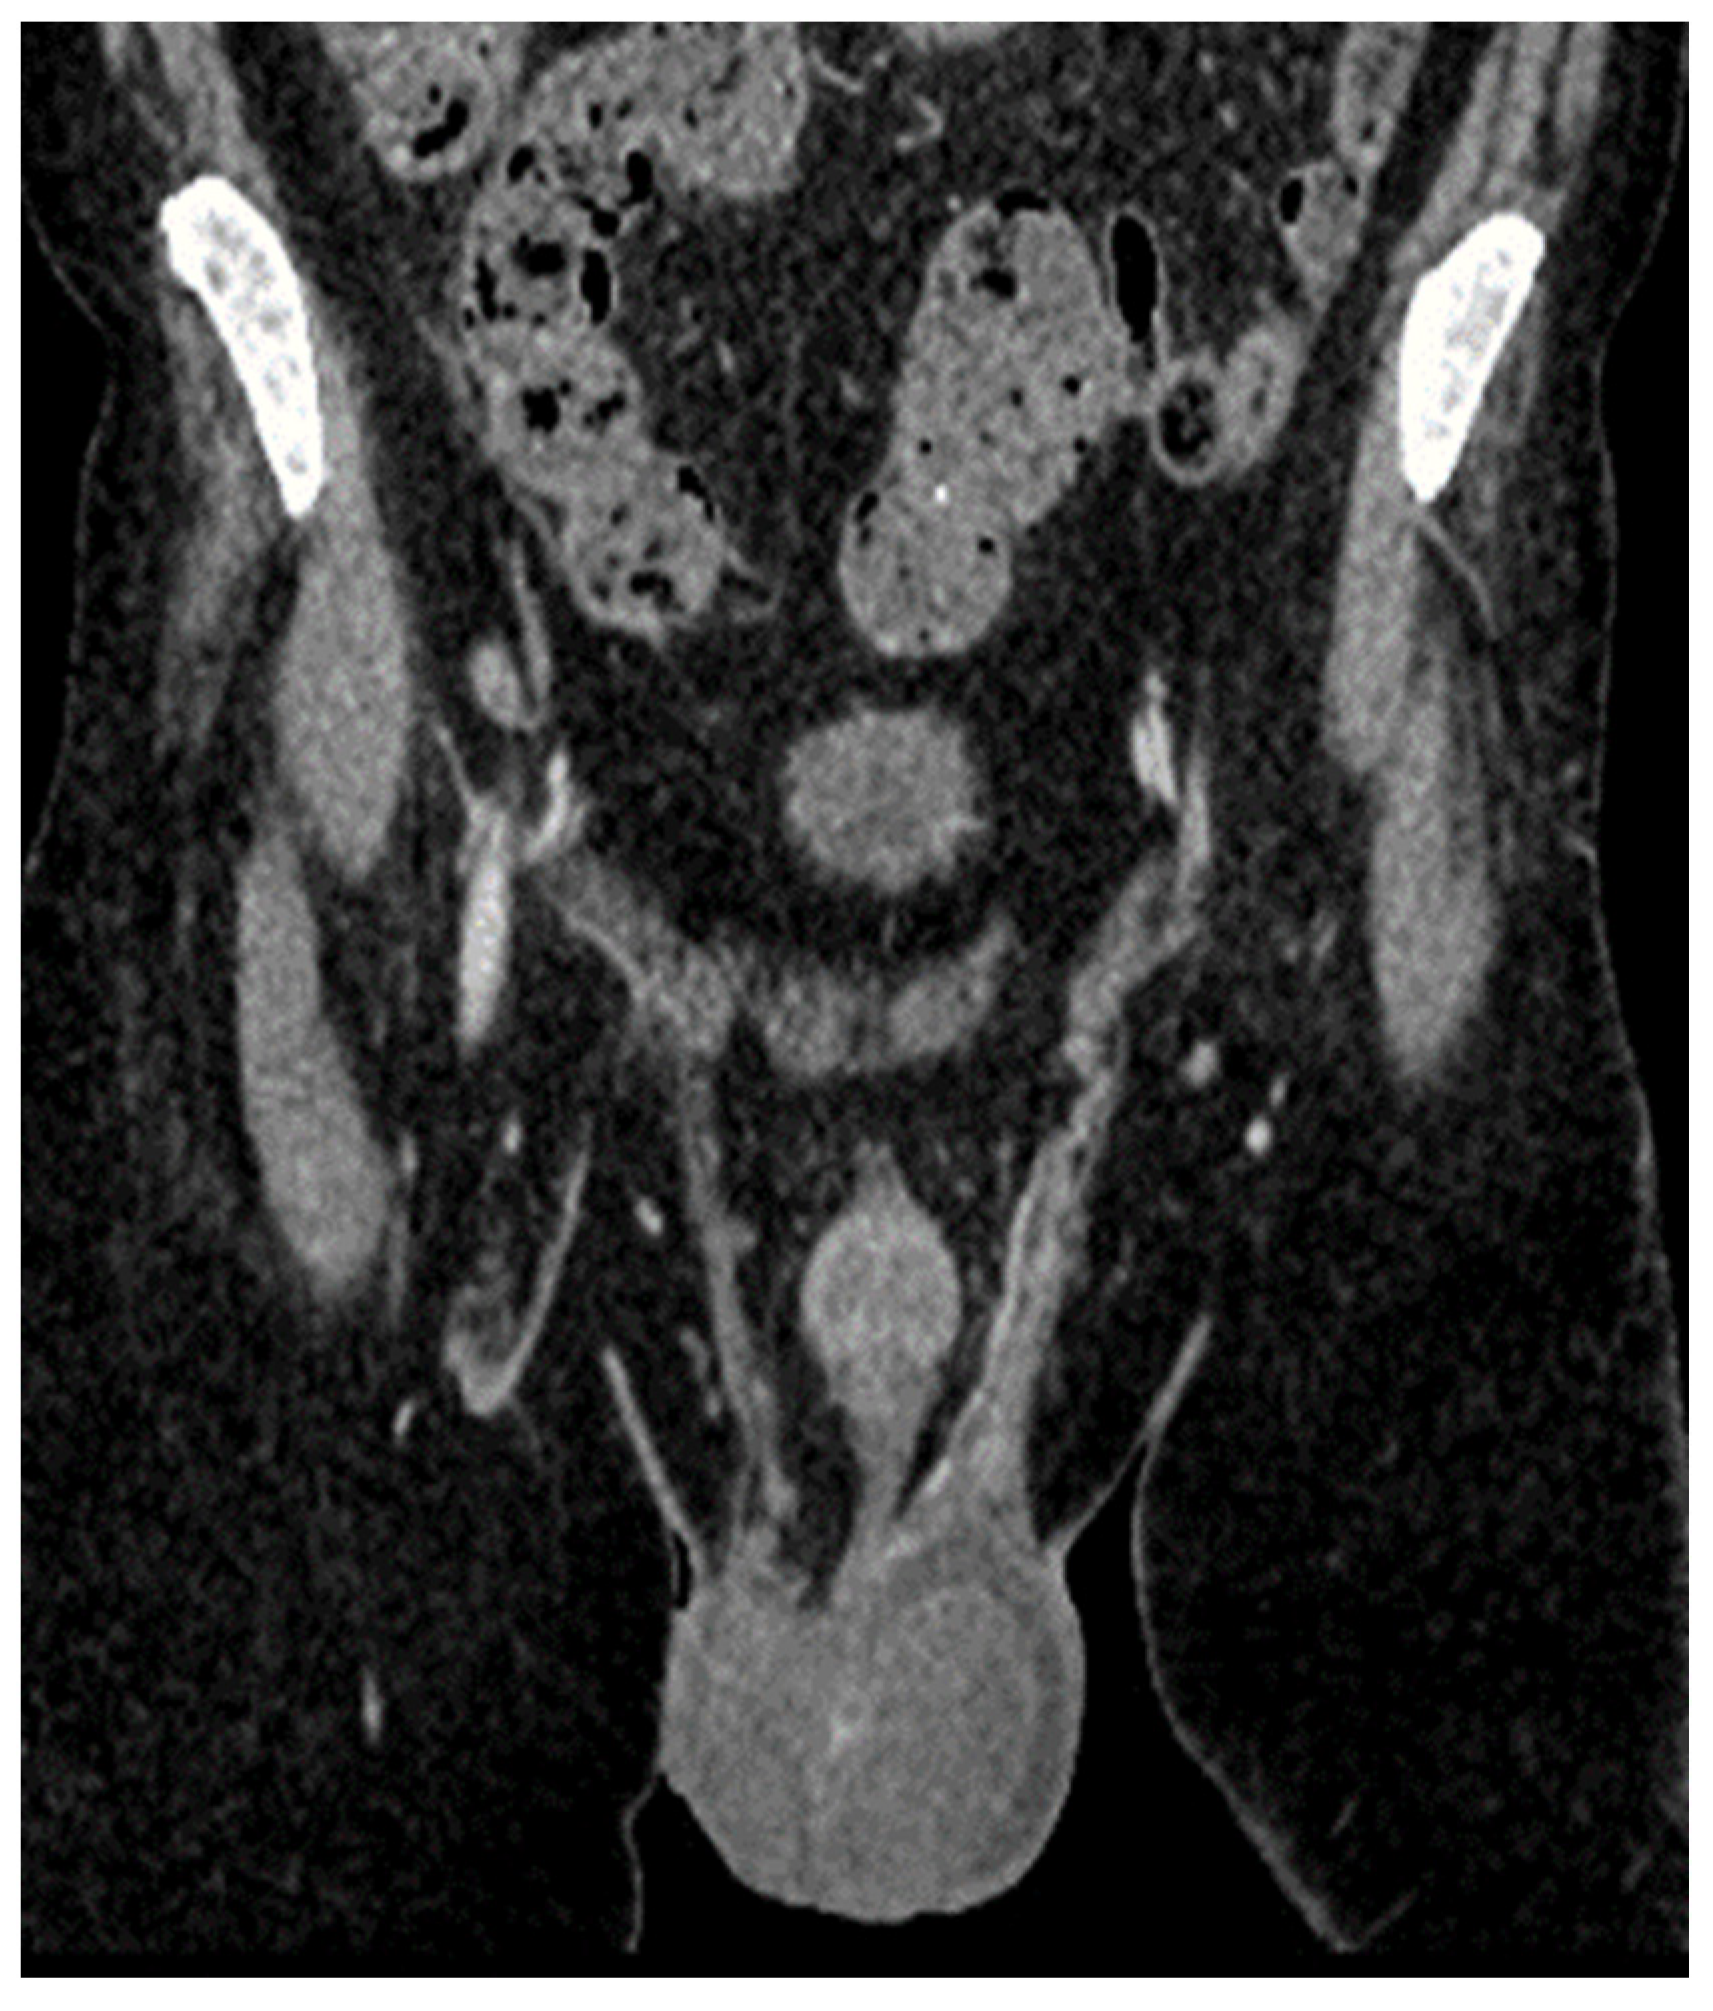

| January 2023 | second extramedullary relapse bilateral ocular left eye clinically, imaging, and biopsy demonstrated right eye demonstrated by imaging | methotrexate, asparaginase, calcium folinate radiotherapy, 30 gy/15 sessions result: imaging complete remission |

| 2 May 2023 | third emr: cardiac and colonic mass (+cns?) | nelarabine+cyclophosphamide+ etoposide |